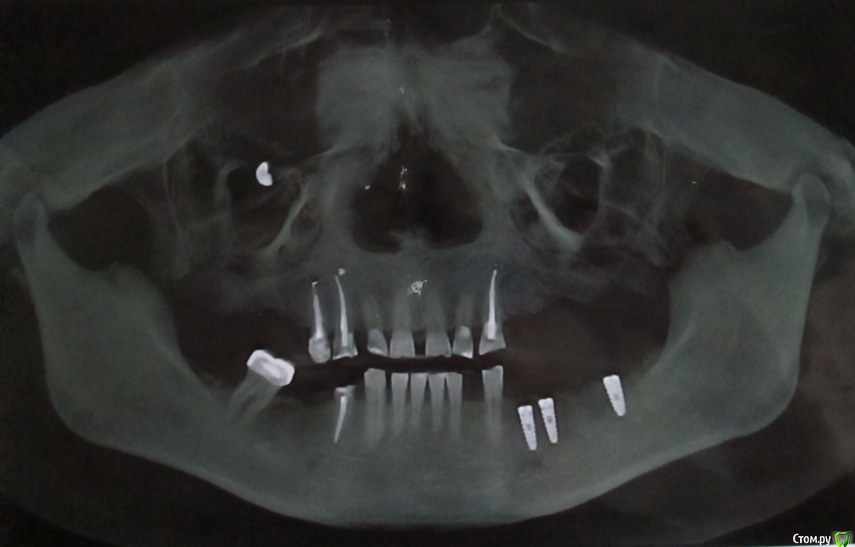

лелька1705 Опубликовано 24 января, 2015 Поделиться Опубликовано 24 января, 2015 (изменено) Одни врачи говорят без проблем имппланты, другие говорят, что никак не возможно, только съемный протез. Как бы понять, кто прав. Развейте сомнения, пожалуйста. Спасибо! Изменено 24 января, 2015 пользователем лелька1705 Ссылка на комментарий

diesel87 Опубликовано 25 января, 2015 Поделиться Опубликовано 25 января, 2015 Не вижу проблем по обеим челюстям, высота позволяет, надо смотреть на ширину, но и это вопрос решаемый, Ссылка на комментарий

лелька1705 Опубликовано 26 января, 2015 Автор Поделиться Опубликовано 26 января, 2015 (изменено) Верно то, что после илиВ том-то и дело, что врач мне нравится ))Пока поставлено три импланта, по-моему все хорошо. Затем планируется: коронки на передние верхние зубы, мост на нижней челюсти справа и съемный на верхней. Вопрос! После ношения съемного протеза, возможно будет установка имплантов? Все-равно нужно время, денег заработать Спасибо! Изменено 26 января, 2015 пользователем лелька1705 Ссылка на комментарий